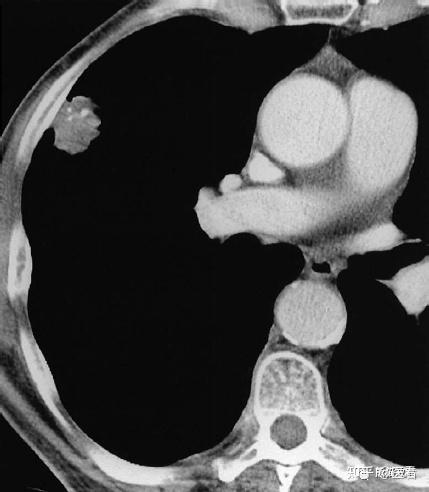

肺癌胸片影像图片,肺癌ct图片图解

支气管肺癌的钙化在胸片上很少显示,6%~10%的肿瘤在ct上可见钙化.

肺癌ct图片图解

肺肿瘤ct图片表现

肺癌图片高清图片ct